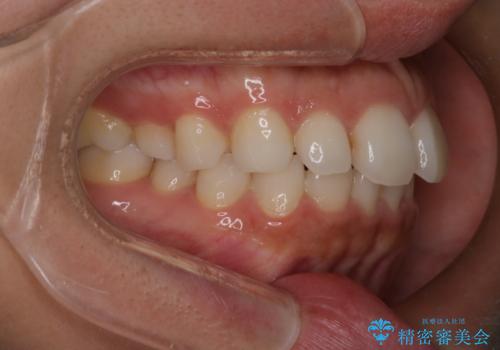

【インビザライン】前歯の後戻りを再矯正

- 前歯が出ていることを主訴に来院されました。検査の結果、口元が標準より出ているわけではなかったため今回はIPRと拡大をし、非抜歯で治療を行いました。

非抜歯でも歯軸の向きを改善したことで前歯が下がり、出っ歯に見えてしまうという主訴が改善しました。